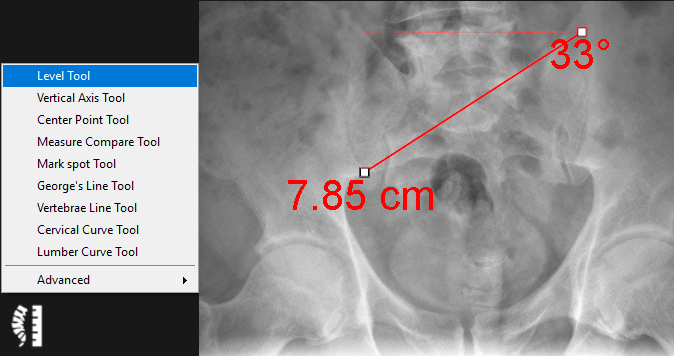

9.5.1. Level Tool

The level tool is used to determine the distance between a drawn line and the horizontal axis as well as the angle between the line and the horizontal axis. Follow the instructions below to use this tool:

1.      Select the ‘Level Tool’ from the chiropractic toolbox.

2.      Click to create the starting point of the line.

3.      Click again to create the end point of the line.

4.      To adjust either of the line points− simply click on the point and drag to the new position.

5.      The distance between the drawn line and the horizontal axis will be displayed as well as the angle between te drawn line and horizontal level.

An example of this tool is shown below: